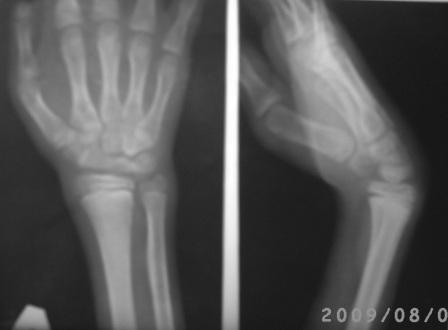

Я остеотомию костей запястья раньше не делал, т.е. не знаю технику, доступа, поэтому планировал произвести укорачиваюшую остеотомию в дистальном метафизе костей п/плечья , укорочение сух.разгибателей кисти, по возможности транспозиция сух.сгибателей кисти и фиксация аппаратом Илизарова или гипсовой повязкой. Что интересно при попытке активного разгибания кисти, сгибательная деформация увеличивается!(см фото)